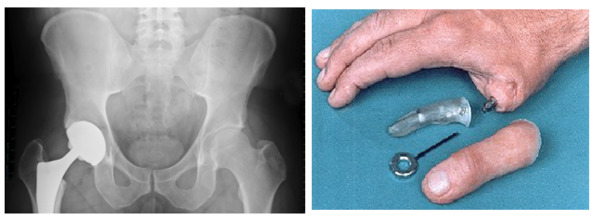

Суставной имплантат

Суставной имплантат

Имплантация суставов и их частей (артропластика). В настоящее время искусственным суставом можно заменить плечевой, локтевой, коленный или бедренный суставы. Возможна имплантация искусственной кисти и суставов пальцев кисти. Реже имплантируют искусственные суставы плюсны или плюснепредплюсневые суставы и суставы пальцев стопы.